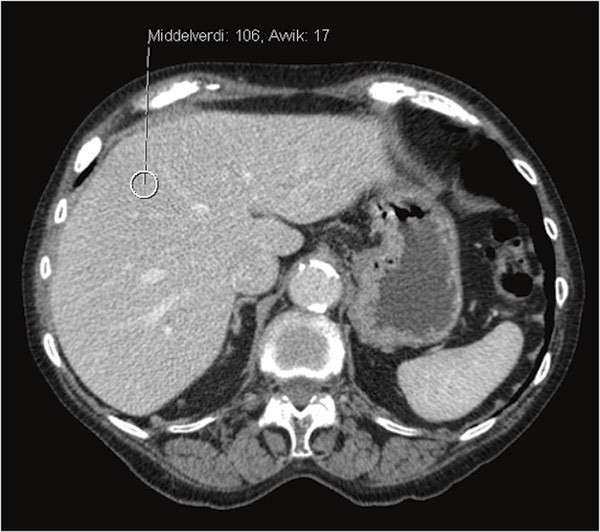

A CT examination of the liver was carried out that showed a pathologically elevated signal with average density 100 HU (Hounsfield units) (Fig. 2, Fig. 3), clearly consistent with iron accumulation in the liver. In the light of these findings, the probability of toxic overload in the liver was regarded as so great that the risk associated with a liver biopsy was not justified. An MRI cor was also carried out at the university hospital, where a T2-weighted image showed maximum pathological values of < 10 ms (> 20 ms), consistent with iron accumulation in the myocardium (Fig. 4). We found no validated method of measuring iron accumulation in the pancreas and thyroid.

Figure 3  CT abdomen without contrast. The image shows high attenuation in the liver, as with iron accumulation (in contrast…

Figure 3 CT abdomen without contrast. The image shows high attenuation in the liver, as with iron accumulation (in contrast to Figure 2)